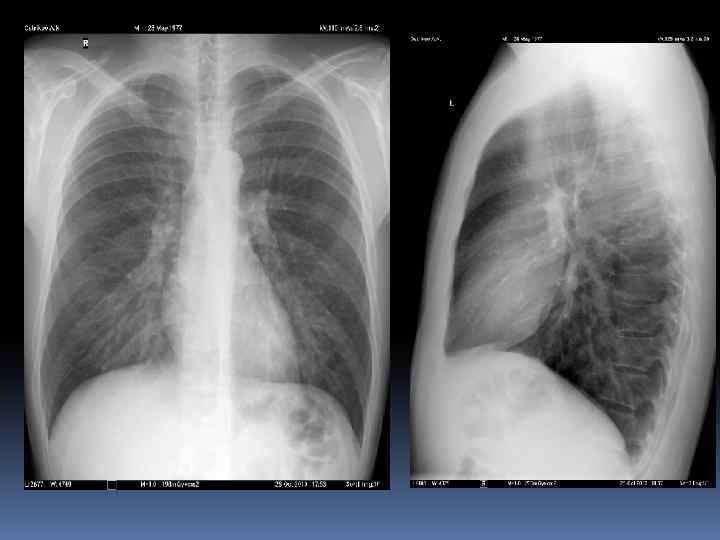

Анатомия ОГК. Пневматизация. Плевра. Междолевые борозды.

Междолевые борозды. Борозда между нижней и верхней, средней долями справа и верхней и нижней долями слева - главная междолевая борозда, имеется с обеих сторон. Справа между верхней и средней долями расположена дополнительная, малая горизонтальная междолевая борозда. Борозды бывают неполными, могут встречаться дополнительные борозды, образующие доли. Борозда состоит из двух слоев плевры, между которыми имеется потенциальная щель. В месте перехода грудной стенки в диафрагму, слои плевры образуют острый угол – синус (заворот): реберно диафрагмальный, реберно – медиастинальный. Задние реберно-диафрагмальные синусы самые глубокие, вытянуты в каудальном направлении.

Междолевые борозды.